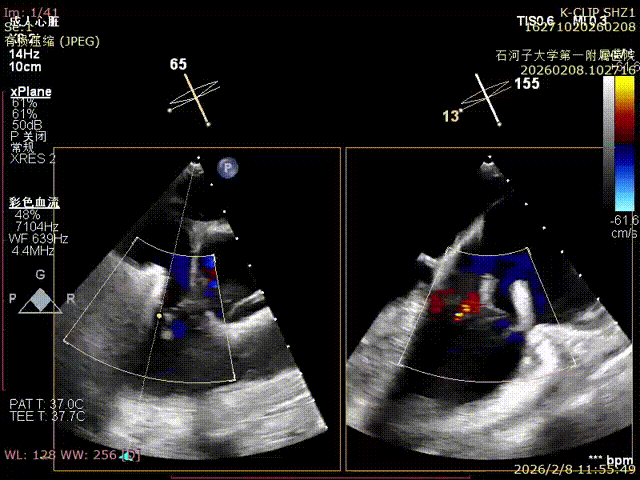

Postoperative

Postoperative reflux

Immediate Postoperative Echocardiographic Assessment: Tricuspid regurgitation was reduced from preoperative grade 4+ to grade 1+, the annulus diameter was reduced to 6.15 cm², and the leaflet coaptation was satisfactory.